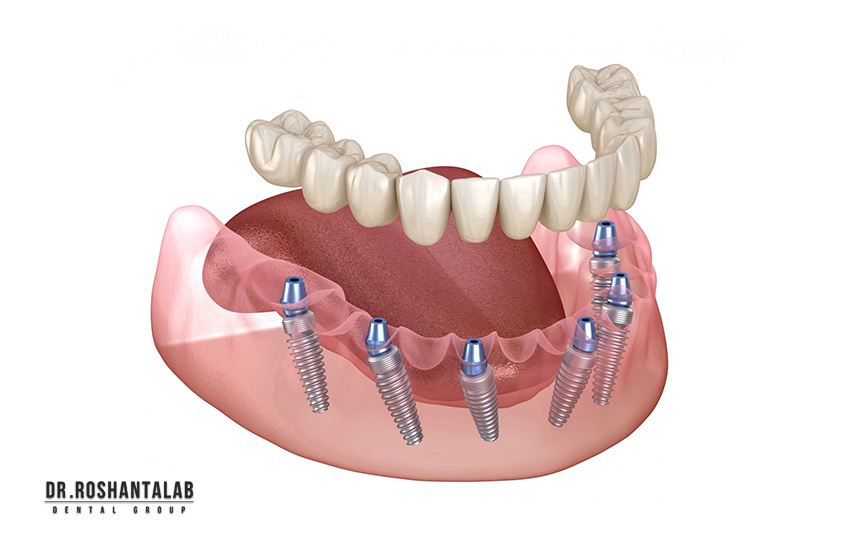

ایمپلنت کامل فک بالا و پایین یا فول آرچ ایمپلنت (Full Arch Implant Restoration)، روشی پیشرفته برای بازسازی تمام دندانهای یک فک یا هر دو فک است که برای سالمندان با بیدندانی کامل یا دندانهای آسیبدیده شدید طراحی شده. این روش شامل کاشت 4 تا 8 پایه ایمپلنت تیتانیومی در استخوان فک است و سپس پروتز ثابت یا نیمهمتحرک (مثل All-on-4، All-on-6 یا اوردنچر) روی آنها نصب میشود. برخلاف پروتزهای سنتی که لغزش دارند و نیاز به چسب، ایمپلنت کامل ثابت است و عملکرد طبیعی جویدن، صحبت کردن و لبخند را بازمیگرداند.

طبق American Dental Association (ADA)، ایمپلنت کامل فک بالا و پایین برای سالمندان بالای ۶۵ سال ایمن است و نرخ موفقیت ۹۵-۹۸٪ دارد، به شرطی که سلامت عمومی (مثل کنترل دیابت) رعایت شود. فک بالا معمولاً به 6-8 پایه نیاز دارد (به دلیل سینوسهای بزرگتر و تحلیل بیشتر استخوان)، در حالی که فک پایین با 4-6 پایه کافی است (استخوان متراکمتر).

در هر فک چند پایه ایمپلنت لازم است؟

- فک پایین: ۴-۶ پایه (تراکم بالا).

- فک بالا: ۶-۸ پایه (نرمتر).

برای جویدن واقعی به چند پایه ایمپلنت در فک بالا و پایین لازم است؟

- فک پایین: ۴ پایه (All-on-4) برای جویدن ۹۰٪، ۶ پایه برای ۹۵٪.

- فک بالا: ۶ پایه برای ۹۰٪، ۸ پایه برای ۹۵٪.

۱. روش All-on-4 (۴ پایه برای هر فک)

در این روش، ۴ پایه تیتانیومی (۲ جلو، ۲ عقب زاویهدار) در هر فک کاشته میشود و پروتز ثابت ۱۲-۱۴ دندانی روی آن نصب میگردد. مناسب برای استخوان متوسط، جراحی در ۱ روز، بهبودی ۳-۶ ماه.

۲. روش All-on-6 (۶ پایه برای هر فک)

۶ پایه برای توزیع بهتر فشار، ایدهآل برای جویدن سنگین یا دندانقروچه. پروتز زیرکونیا مونولیتیک، دوام ۲۰+ سال.

۴. روش فول آرچ سنتی (8-10 پایه برای هر فک)

8-10 پایه برای حداکثر استحکام، پروتز ثابت کامل. برای موارد پیچیده با پیوند گسترده.